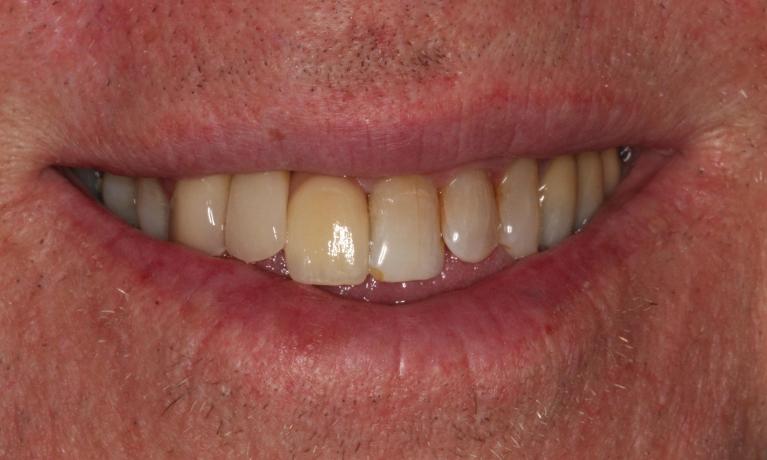

This young dad had four congenitally missing upper teeth. He had a quick orthodontic treatment and a large span bridge placed in as a teenager. He never smiles with teeth showing.

After many years of wear and tear, some of the work started to break and fail. We removed the defective bridges, managed to save all the existing teeth and placed four implant supported crowns in. The patient is very happy to be able to smile confidently now.